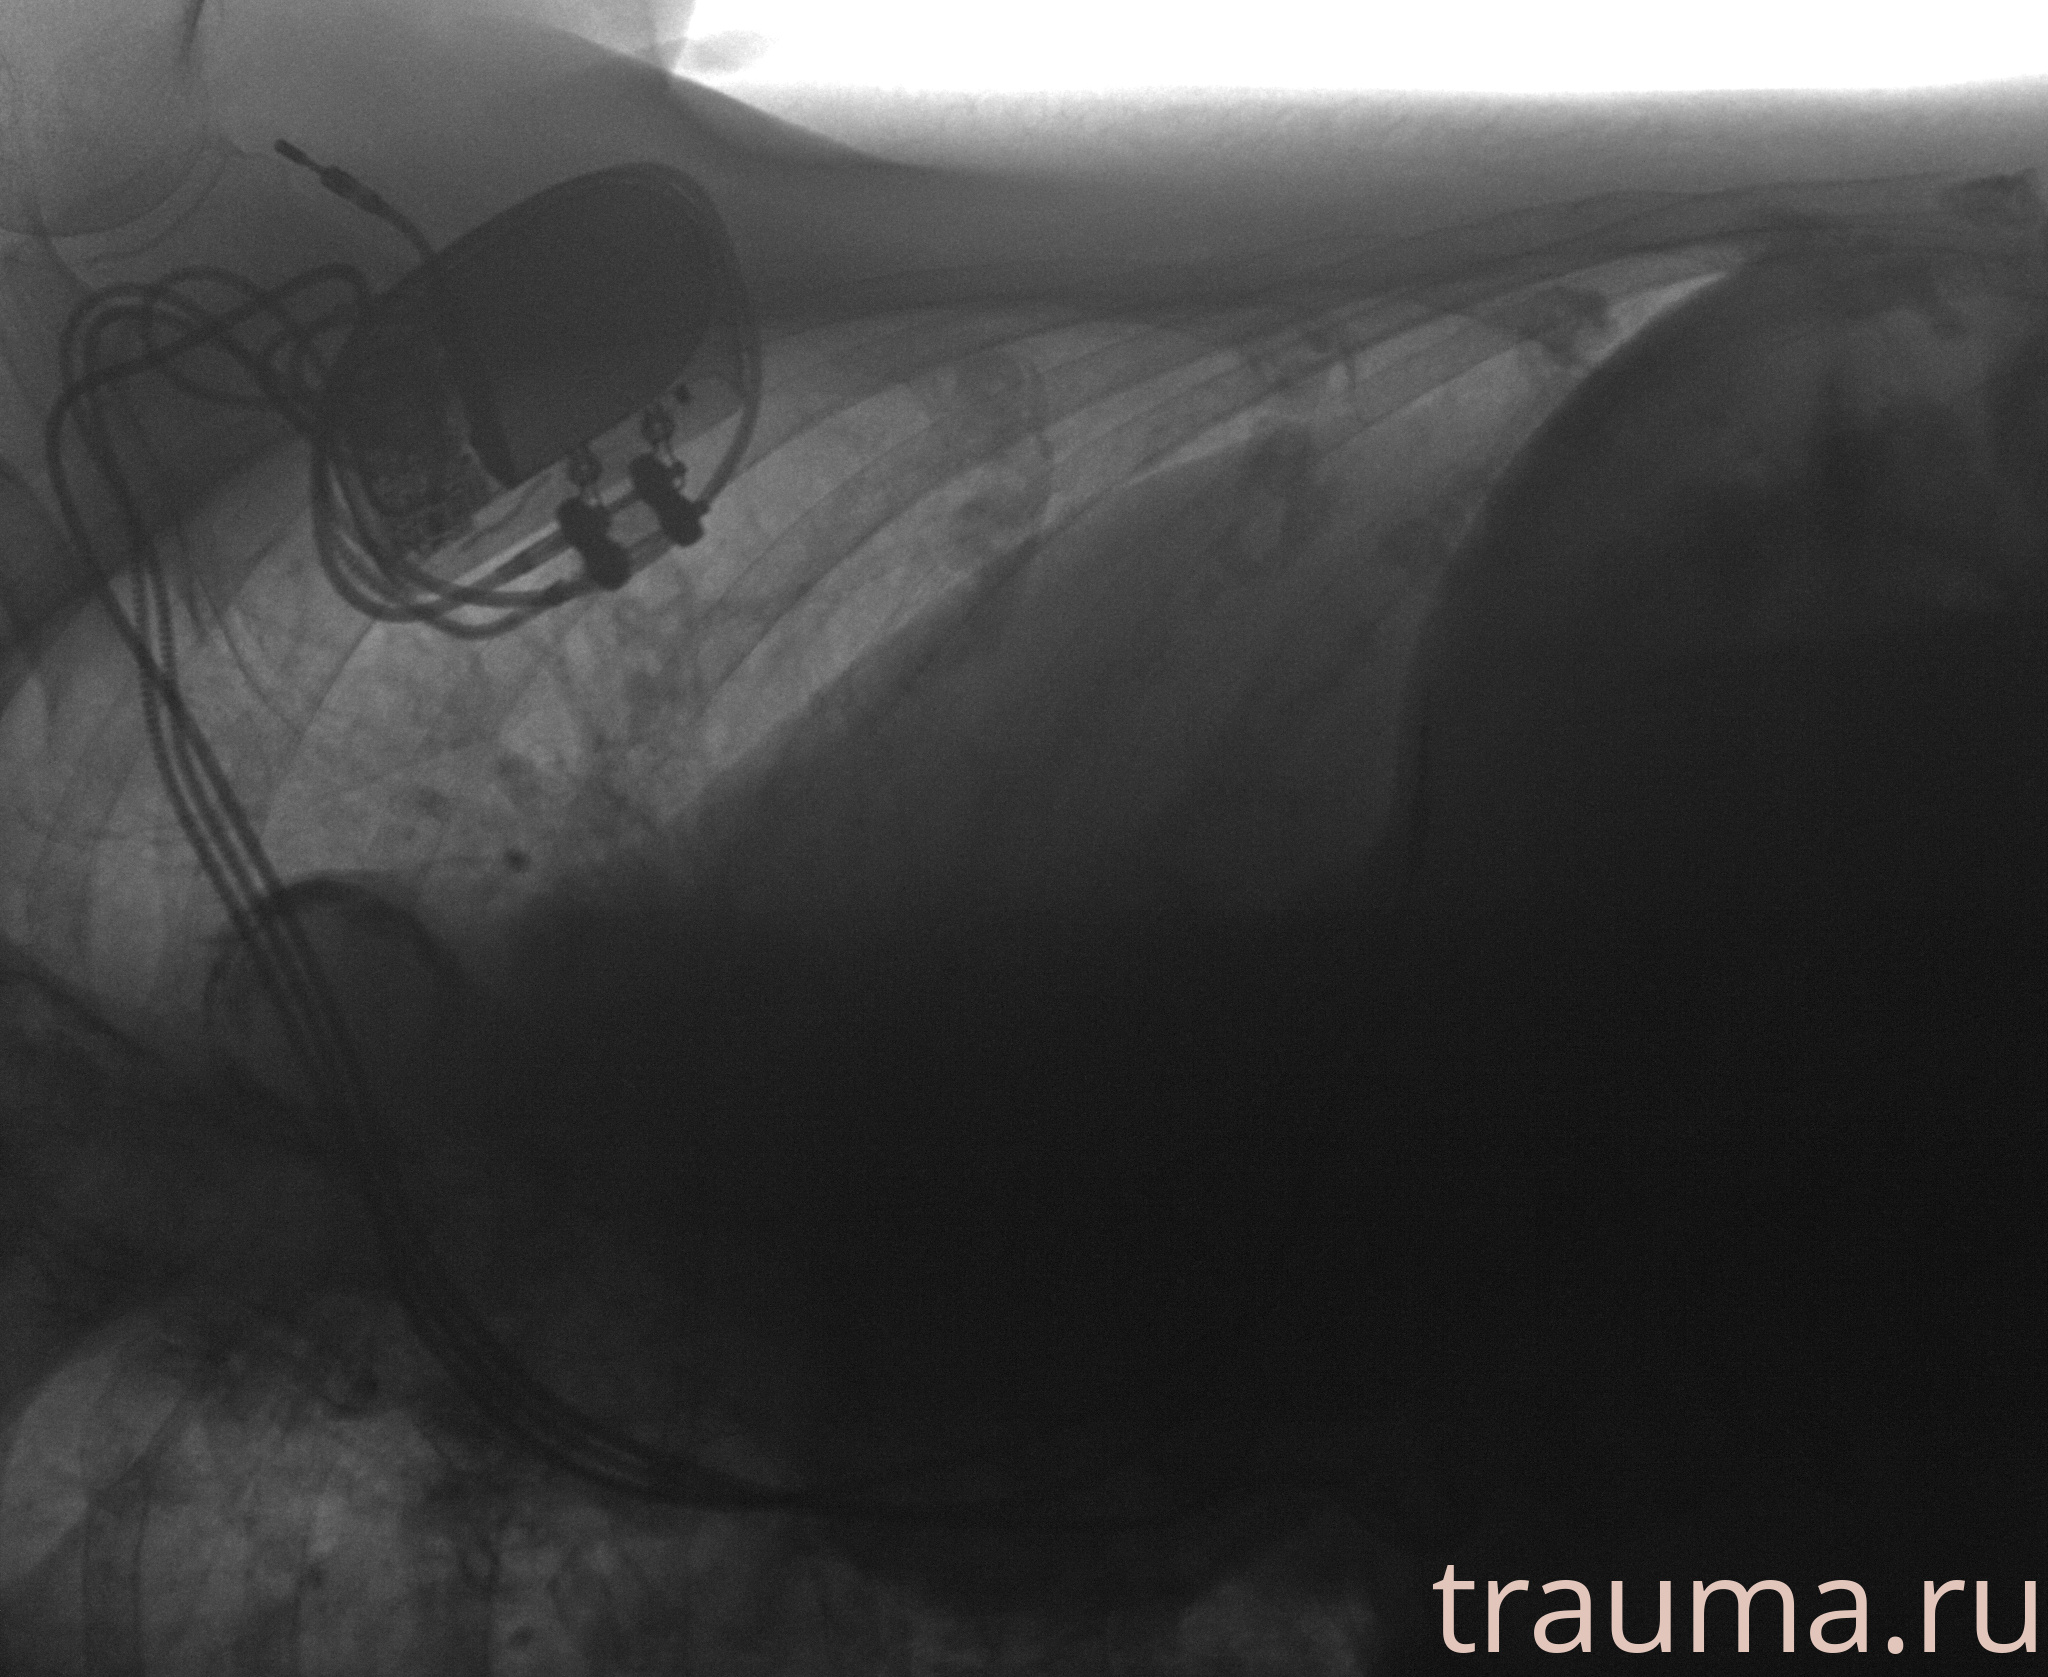

Рентгенограммы

Рентген на дому: по вашему адресу приезжает врач-рентгенолог, травматолог-ортопед с мобильным рентгеновским аппаратом, проводит диагностику травмы или заболевания, делает необходимые рентгенограммы, дает рекомендации по дальнейшему лечению. Получить качественные снимки в домашних условиях возможно благодаря уникальной методике, разработанной МосРентген Центром для института  Склифосовского

при переломе шейки бедра и пневмонии от компании МосРентген Центр - партнера Института имени Склифосовского